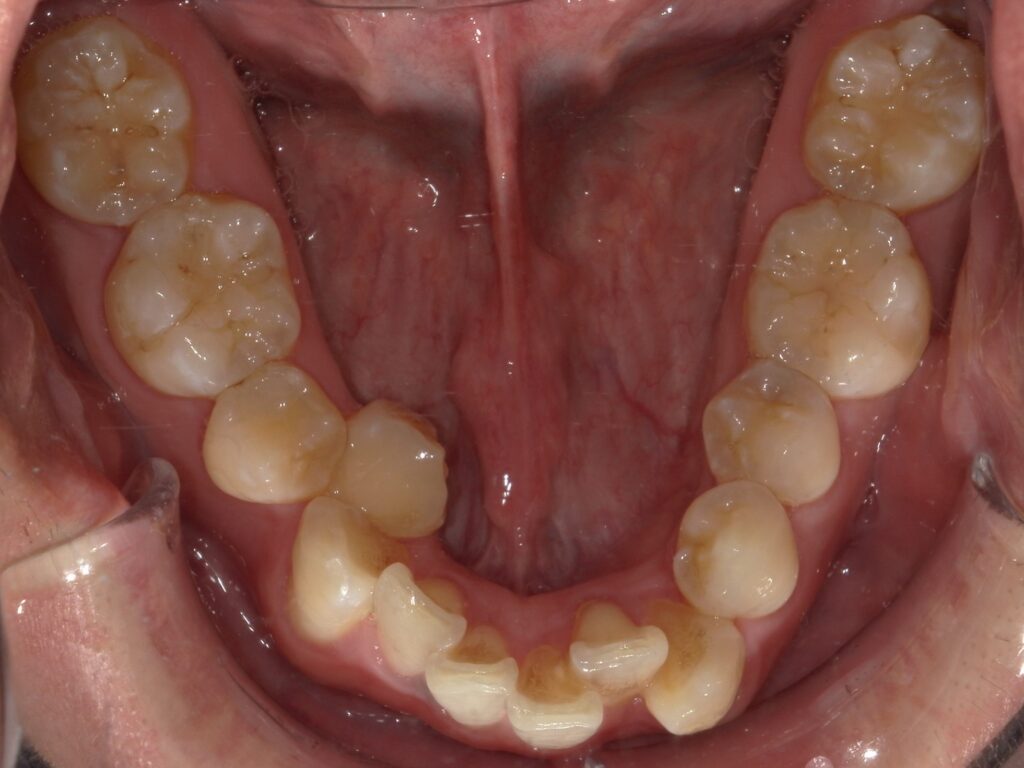

Before

After

ガタつき / 八重歯

- 30代男性

- 主訴:ガタつき

- 矯正方法:インビザラインの抜歯矯正

- 治療期間:12ヶ月

- 治療費:935,000円

- その他ご要望:お仕事柄、ワイヤーではなく目立たないマウスピース型をご希望。分割払いをご希望。

- 詳しくはこちら

ご相談内容 ガタつきが気になると30代男性からのご相談 現状と治療方針 重度のガタつきが見られます。八重歯や内側に倒れた歯があり、顎のスペースに対して歯が並ぶスペースが不足していたためインビザラインで片側の抜歯矯正を行いました。 治療結果 ガタつきを12ヶ月で改善することができました。 振り返り 今回の患者様はガタつきが重度だったため、片側の抜歯矯正を選択しました。ご本人は治療期間が2年ほどかかると思われていたようで、このガタつきが12ヶ月で改善したことに大変喜ばれていました。人前に出るお仕事柄、目立つ装置は避けたいとのご希望があり、目立たないマウスピースで改善することができました。 リスク・副作用 マウスピースの装着時間を守っていただけないと矯正治療に時間がかかり、場合によっては治療がうまく進まない可能性があります。